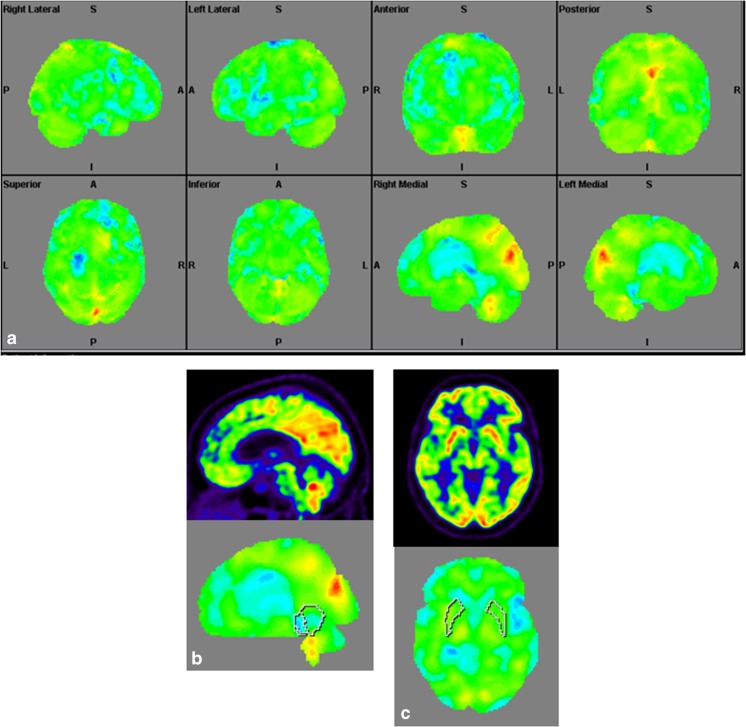

Structural Brain Imaging and [18F] FDG PET

The imaging data are summarized in Table 1 and are shown in Figs. 2, 3, 4, 5, 6, 7, and 8. Brain MRI revealed atrophy of the vermis and supratentorial white matter hyperintensities (WMH) in patients III:1 and III:2 and to a lesser degree in the index case (Figs. 2, 3, and 5). These WMH were particularly widespread in III:1 (Fig. 2). The index case was not affected by any other comorbidity usually associated with WMH, suggesting that these abnormalities may be an underlying feature of SCA19/22. WMH were not evident in the youngest patient (V:1). [18F] FDG PET revealed hypometabolism in the entire cerebellum, thalamus, prefrontal cortex (PFC), and parietal regions of the index case (IV:1) (Fig. 6). Her mother had reduced glucose metabolism not only in the PFC but also in the vermis as wells as in the motor and temporal cortex (Fig. 4). The youngest patient (V:1) had hypometabolism in the PFC, parietal, and inferior temporal regions but surprisingly not in the cerebellum (Fig. 8). In the latter structure, atrophy of the vermis was evident (Fig. 7).

Fig. 4.

Surface projections (3DSSP) of brain [18F] FDG PET findings for patient III:2. a Widespread hypometabolism in the prefrontal cortex and some areas of the motor and temporal cortices is evident. Metabolism is also reduced in the vermis but normal in the cerebellar hemispheres. b Midsagittal image shows reduced FDG uptake in the vermis (upper case) as compared to the reference values in VOI templates (lower case). c Coronal image shows normal FDG uptake in the putamen (upper case) as compared to the reference values (lower case)